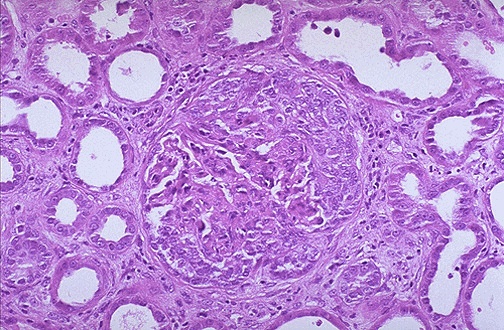

| Here is another glomerulus with epithelial crescents squashing the glomerular tufts from all sides. RPGN may be idiopathic or may result from SLE, post-infectious GN (as in some cases of post-infectious GN), from various types of vasculitis, and from Goodpasture syndrome. |